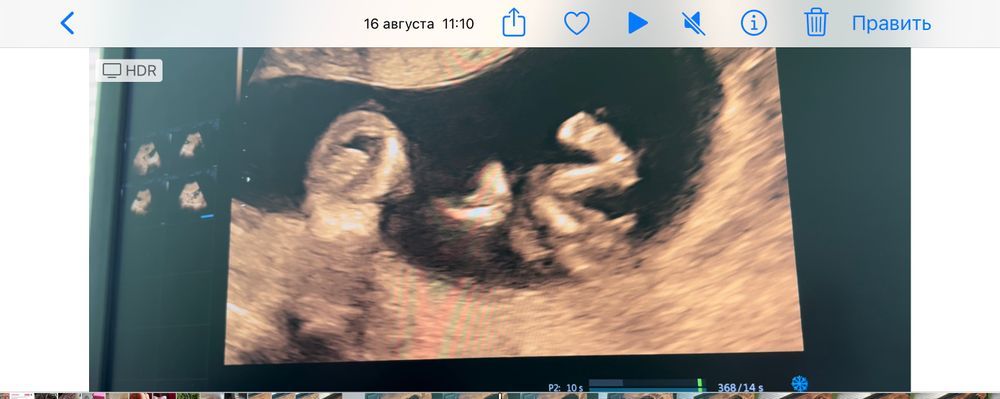

А наш звенел своими бубенцами 😂

12.10.2022

Надежда , на какой неделе начал звенеть?😁

Li, на 12 😁